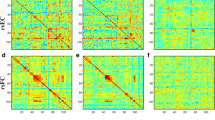

Whole-brain FCs were calculated using DPABI software. Each subject’s correlation matrix was acquired by calculating the Pearson’s correlation coefficients of the relationship of each voxel’s time series with all other voxels’ time series within a predefined gray matter mask, which was acquired by thresholding the gray matter probability map in statistical sarametric sapping (SPM) (https://www.fil.ion.ucl.ac.uk/spm) (probability > 0.2) and included all gray matter voxels in the whole-brain [23]. Each correlation matrix was normalized using a Fisher z-transformation. FC strength assesses the weight (accumulation) of functional connections, and therefore was calculated as the sum of z values between each voxel and all other voxels [24]. To assess the effects of anatomical distance on FC, we divided FCs into short- and long-range FCs. Short- range FC was defined as the sum of z values between a given voxel and other voxels with anatomical distances below 75 mm, whereas long-range FC refers to anatomical distances over 75 mm. The anatomical distances between voxels referred to the euclidean distance Dij (in mm) between their MNI coordinates: Dij = \(\sqrt{{({\mathrm{x}}_{\mathrm{i}}+{\mathrm{x}}_{\mathrm{j}})}^{2}+{({\mathrm{y}}_{\mathrm{i}}+{\mathrm{y}}_{\mathrm{j}})}^{2}+{({\mathrm{z}}_{\mathrm{i}}+{\mathrm{z}}_{\mathrm{j}})}^{2}}\), xi, yi, zi and xj, yj, zj are the stereotaxic coordinates of the centroids for voxels i and j. For example, the short-range FC strength of voxel 1 (D < 75 mm): 0.88 + 0.6 + 0.9, and long-range FC strength of voxel 1 (D > 75 mm):0.62 + 0.68 + 0.73 + 0.85 + 0.95 + 0.79 (Fig. 2). The euclidean distance used in this study provides an approximate reflection of the true physical distance (axonal length) of connections between voxels and has been applied in previous studies [24,25,26]. FCs were divided into four categories: short-range positive FC (spFC), short-range negative FC (snFC), long-range positive FC (lpFC), and long-range negative FC (lnFC). Given the ambiguous explanation of negative correlations and detrimental effects of negative correlations on test–retest reliability, the present FC analyses were restricted to positive correlations (spFC and lpFC) by setting negative correlations to 0 [27,28,29].

Six brain regions (1 = left precentral/postcentral gyrus [spFC], 2 = left cerebellum Crus I/VI, 3 = left IPL, 4 = left precentral/postcentral gyrus [lpFC], 5 = left thalamus, and 6 = right thalamus/caudate) with abnormal spFC and lpFC values were used to SVM analysis. The accuracy of each brain region was as follows: 1 = 80.769% (63/78); 2 = 75.641% (59/78); 3 = 70.513% (55/78); 4 = 76.923% (60/78); 5 = 75.641% (59/78); 6 = 73.077% (57/78) (Fig. 5). The lower spFC of the left precentral/postcentral gyrus might be used to distinguish OCD from HCs with an accuracy of 80.77%, specificity of 81.58%, and sensitivity of 80.00% (Fig. 6). A permutation test showed that the global accuracy was 0.825 (p < 0.001) for discriminating patients with OCD from HCs using spFC values of region 1. Confounder variables (i.e., age, FD, sex, and education level) were also used as characteristics for the SVM analysis. The classification accuracies were as follows: age, 56.4%; FD, 55.1%; sex, 48.7%; and education level, 51.3%.

Accuracies of SVM using six brain regions with abnormal spFC and lpFC in distinguishing patients with OCD from HCs. The SVM results showed that the accuracy of region 1 is the highest. 1 = left precentral/postcentral gyrus (spFC), 2 = left cerebellum Crus I/VI, 3 = left inferior parietal lobule, 4 = left precentral/postcentral gyrus (lpFC), 5 = left thalamus, 6 = right thalamus/caudate. SVM = support vector machine; spFC = short-range positive functional connectivity; lpFC = long-range positive functional connectivity; OCD = obsessive–compulsive disorder; HCs = healthy controls